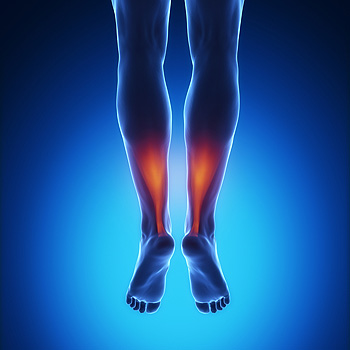

Achilles Tendonitis Can Turn Into Tendonosis

The Achilles tendon is a thick band of fibrous tissue located at the back of the lower leg. It connects the calf muscle to the heel bone and allows us to walk by raising the heel off of the ground. Repetitive stress placed on this tendon during activities such as running, playing high impact sports, and working on your feet can cause the tendon to become injured. Initially, the Achilles tendon may become inflamed in a condition known as Achilles tendonitis. An inflamed Achilles tendon can be painful, tender, and stiff. If left untreated, Achilles tendonitis could become chronic and lead to a degeneration of the tendon known as Achilles tendonosis. This condition makes the tendon lose its organized structure and makes it more likely to develop microscopic tears that cause chronic pain and may restrict mobility. Achilles tendonosis can also make a full rupture more likely. If you experience pain in your calf muscles, it is strongly suggested that you seek the care of a podiatrist who can diagnose and treat your condition and prevent further injury.

The Achilles tendon is a thick band of fibrous tissue located at the back of the lower leg. It connects the calf muscle to the heel bone and allows us to walk by raising the heel off of the ground. Repetitive stress placed on this tendon during activities such as running, playing high impact sports, and working on your feet can cause the tendon to become injured. Initially, the Achilles tendon may become inflamed in a condition known as Achilles tendonitis. An inflamed Achilles tendon can be painful, tender, and stiff. If left untreated, Achilles tendonitis could become chronic and lead to a degeneration of the tendon known as Achilles tendonosis. This condition makes the tendon lose its organized structure and makes it more likely to develop microscopic tears that cause chronic pain and may restrict mobility. Achilles tendonosis can also make a full rupture more likely. If you experience pain in your calf muscles, it is strongly suggested that you seek the care of a podiatrist who can diagnose and treat your condition and prevent further injury.

The Achilles tendon is a tendon that connects the lower leg muscles and calf to the heel of the foot. It is the strongest tendon in the human body and is essential for making movement possible. Because this tendon is such an integral part of the body, any injuries to it can create immense difficulties and should immediately be presented to a doctor.

The Achilles tendon is the strongest tendon in the human body. Its purpose is to connect the lower leg muscles and calf to the heel of the foot. This tendon is responsible for facilitating all types of movement, like walking and running. This tendon provides an enormous amount of mobility for the body. Any injuries inflicted to this tissue should be immediately brought up with a physician to prevent further damage.

The most common injuries that can trouble the Achilles tendon are tendon ruptures and Achilles tendinitis. Achilles tendinitis is the milder of the two injuries. It can be recognized by the following symptoms: inflammation, dull-to-severe pain, increased blood flow to the tendon, thickening of the tendon, and slower movement time. Tendinitis can be treated via several methods and is often diagnosed by an MRI.

An Achilles tendon rupture is trickier to heal, and is by far the most painful injury. It is caused by the tendon ripping or completely snapping. The results are immediate and absolutely devastating, and will render the patient immobile. If a rupture or tear occurs, operative and non-operative methods are available. Once the treatment begins, depending on the severity of the injury, recovery time for these types of issues can take up to a year.